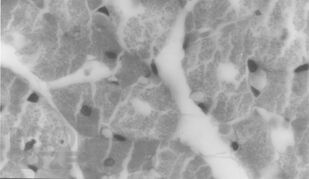

В учебно-методическом пособии приведены изменения микроциркуляции, дисциркуляторные и дистрофические изменения сердца, легких, диафрагмы и спинного мозга в раннем послеоперационном периоде на позвоночнике в эксперименте. Рекомендуется для врачей - ортопедов-травматологов, гистологов.